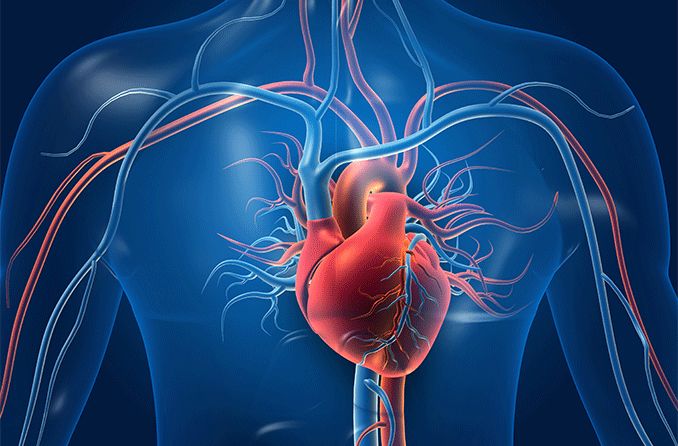

Ayurvedic treatments to naturally regulate blood pressure and promote heart health.